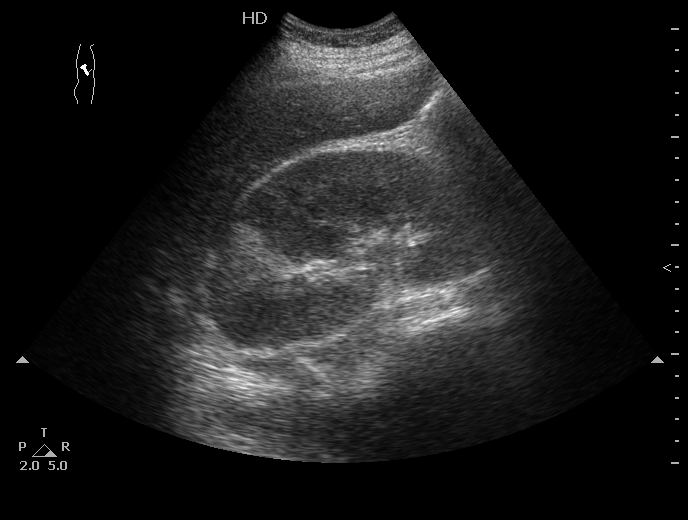

Роженица, во время беременности случилась почечная колика, стентирована.

Боли справа, повышение температуры.

Размеры правой почки 160х80х80мм

Острый правосторонний апостематозный пиелонефрит, формирующиеся абсцессы почки. МКБ, конкремент правой почки.

Пациентка переведена в урологию, где ей проводится консервативное лечение.

Как выглядят собственно апостемы я показать не смогу, так как у меня нет такого замечательного высокочастотного датчика как у вас в детской больнице (вспоминаю сонограммы почек при поликистозной болезни новорожденных здесь на форуме). А вот как выглядит почка с таким заболеванием - см пост 1.

Это - большая почка со сравнительно маленьким центральным эхокомплексом, неравномерно гипоэхогенной паренхимой и отсутствием кортикомедуллярного контраста.